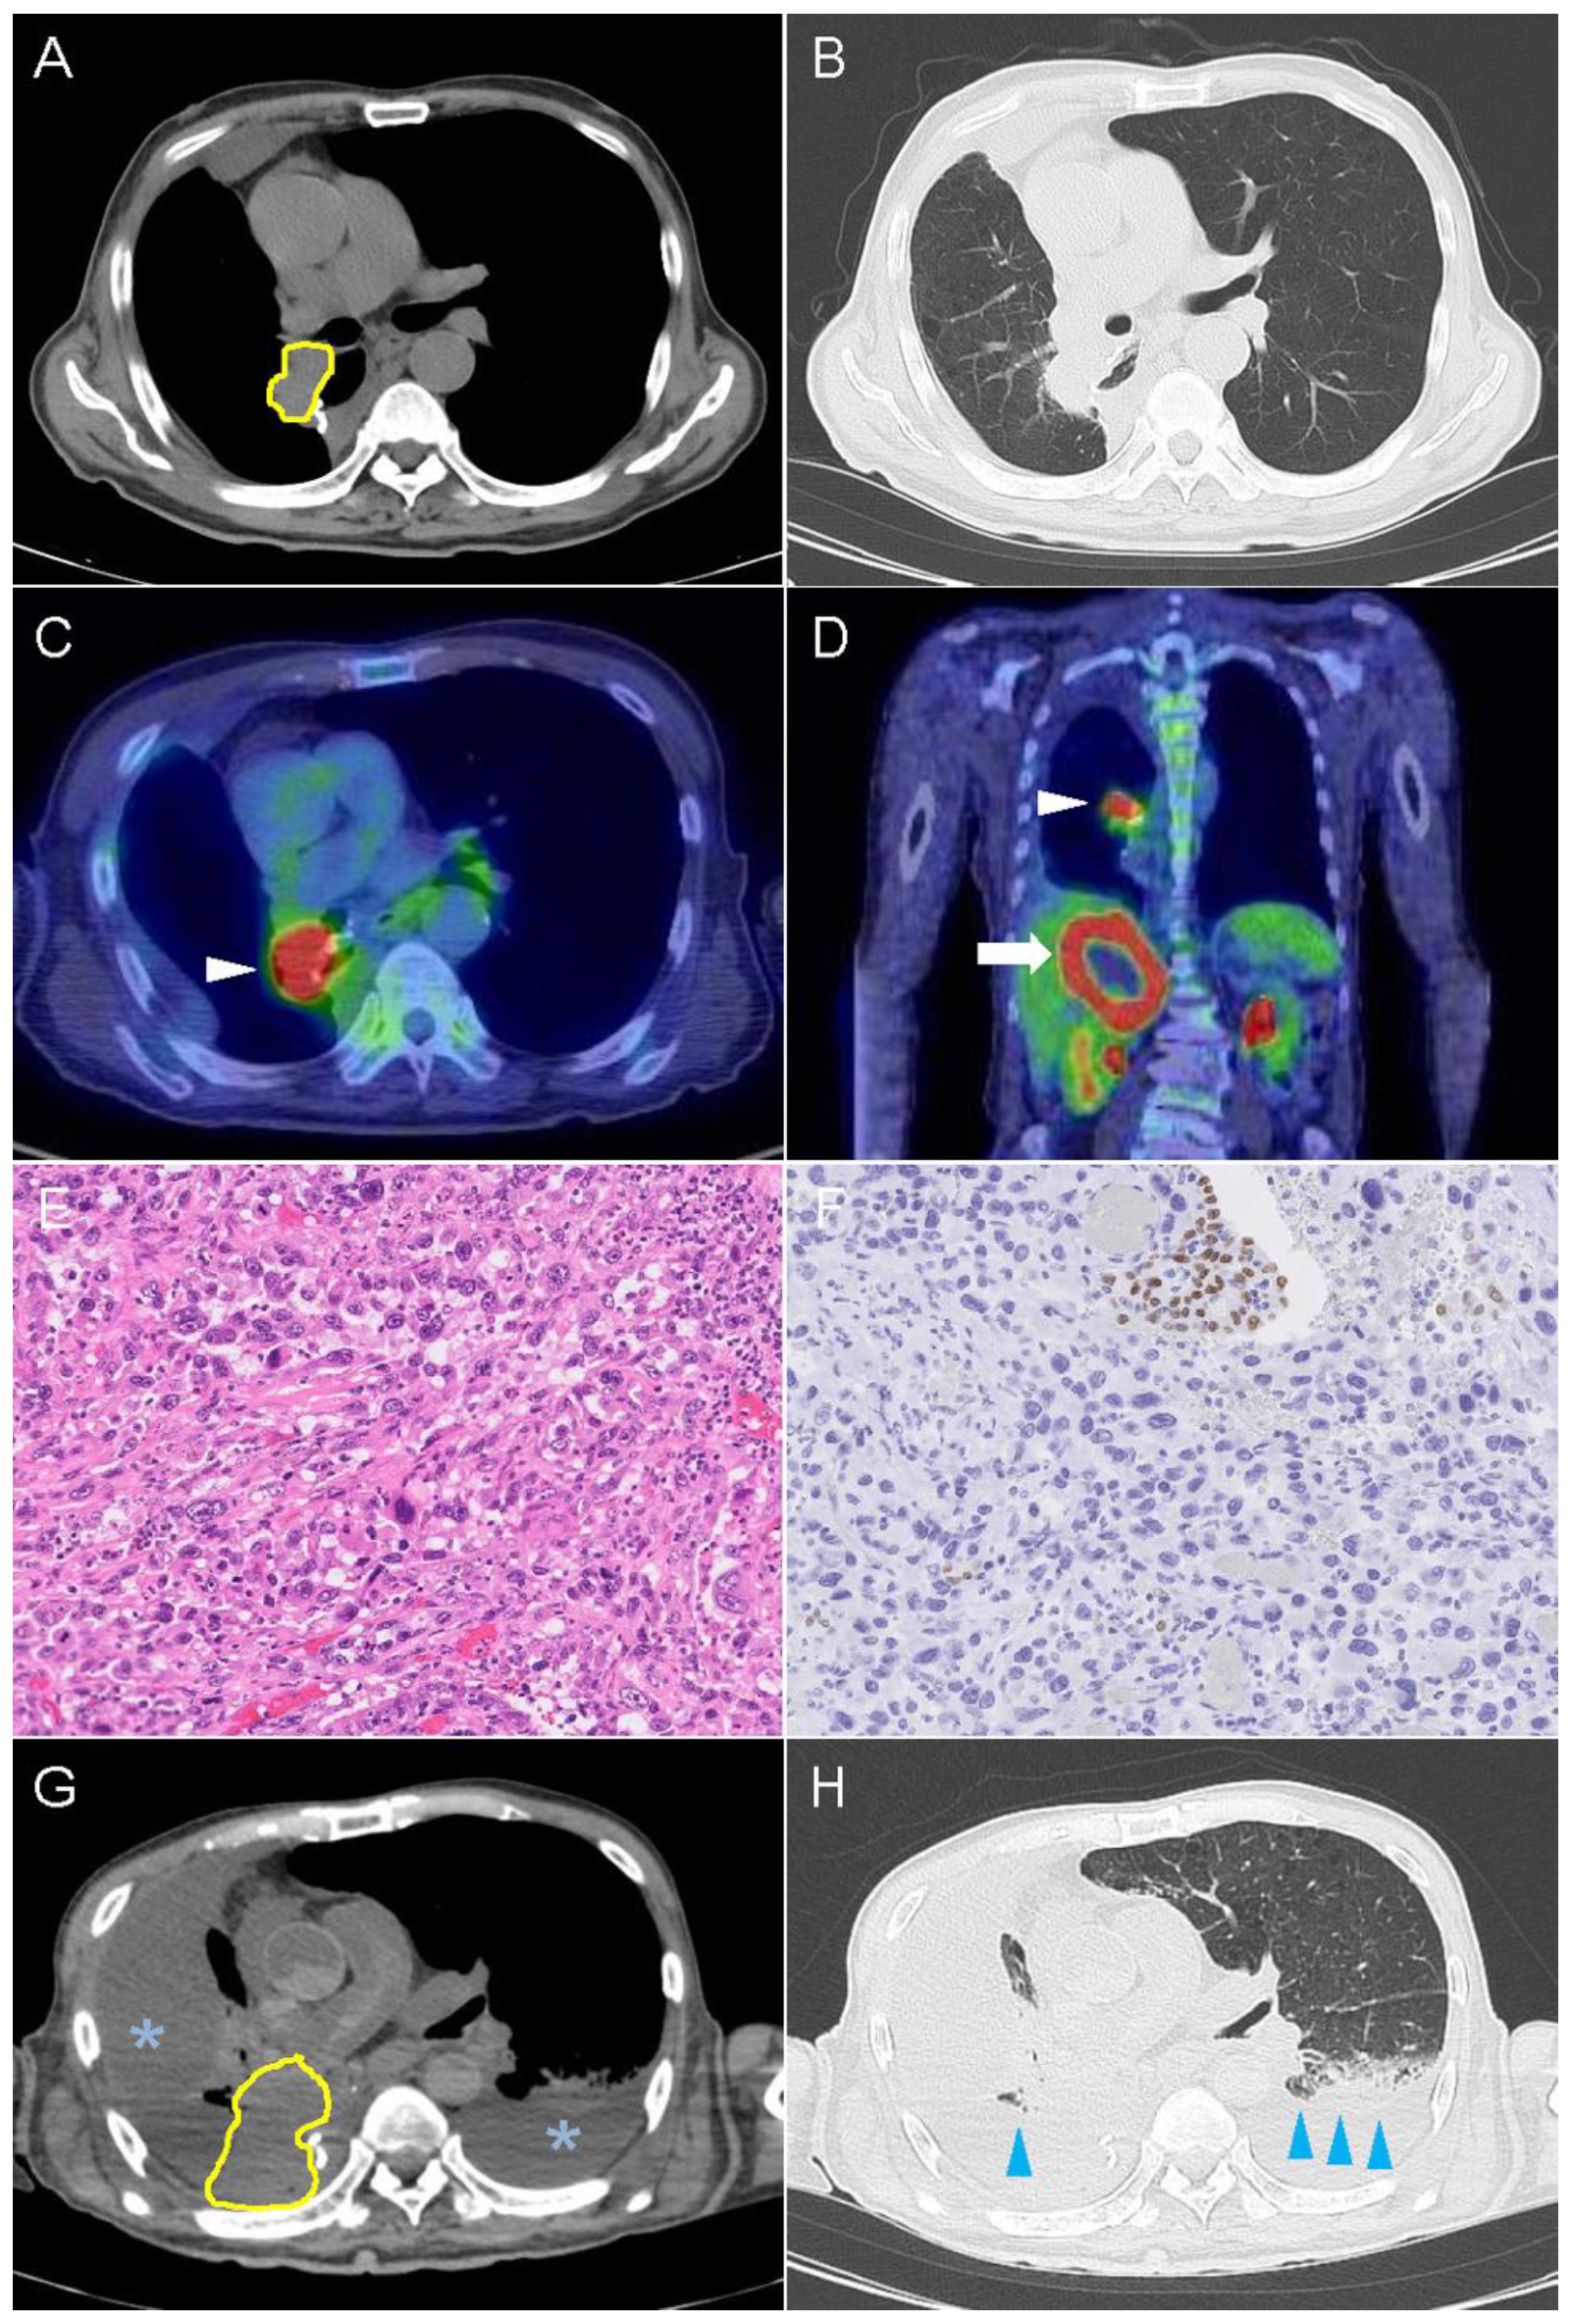

2.2. Case 2